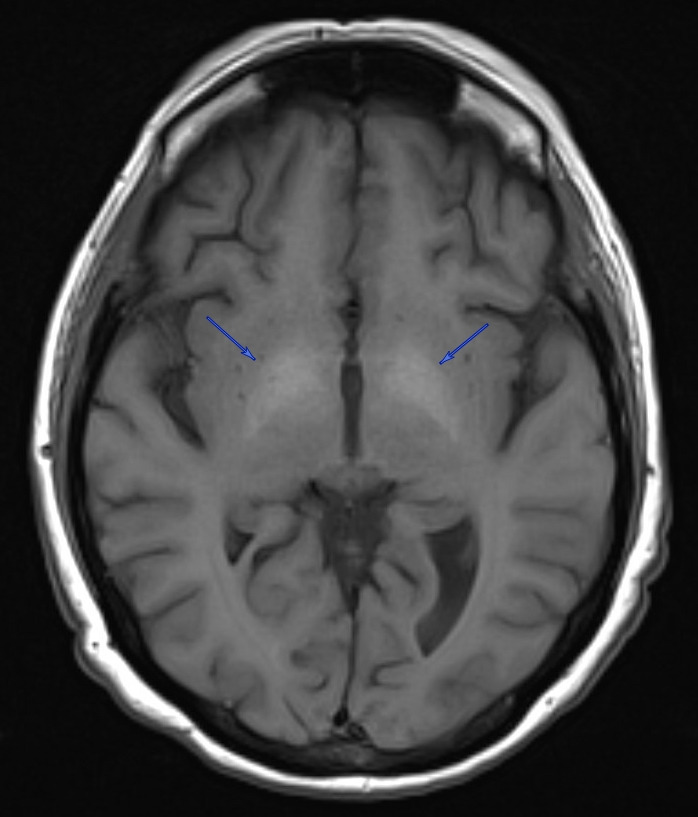

A 50-year-old woman with a history of alcohol use disorder complicated by alcoholic cirrhosis, hepatic encephalopathy, mild Korsakoff syndrome, variceal bleeds, opioid use disorder with chronic pain, attention deficit hyperactivity disorder, major depressive disorder, and hallucinations presented from an alcohol detoxification program with worsening confusion and hallucinations, as well as suffering an unwitnessed fall. Vitals on admission were all stable and within normal limits. The physical exam was largely unremarkable, with the patient oriented only to self and location, and an otherwise intact neurological exam. Notably, gait was not evaluated at the time of admission due to the patient’s high risk of falls. History was limited mainly due to confusion and visual hallucinations. Her pertinent labs at that time showed hemoglobin 10.0 g/dL (normal 11.2 – 14.9 g/dL), MCV 78.4 fL (normal 85.2 – 100.2 fL), ammonia 52 umol/L (normal 1 – 39 umol/L), iron 16 UG/DL (normal 37 – 170 UG/DL), ferritin 18 NG/ML (normal 5 – 204 NG/ML), transferrin saturation 4% (normal 15 – 50%), and ethanol 258 MG/DL (normal 0 MG/DL). Venous blood gas and thyroid-stimulating hormone levels were within normal limits, and urinalysis was negative for signs of infection. CT angiography of the head showed no intracranial abnormalities. She was empirically treated for alcohol withdrawal, hepatic encephalopathy, and Korsakoff syndrome. She was also evaluated by psychiatry for agitation and was started on olanzapine as needed. After a week of admission and resolution of hallucinations and return of baseline mental status, the patient was discharged to a rehab facility, from which she was readmitted a week after for acute encephalopathy; she had been started on amitriptyline at the rehab facility, which was suspected to have caused anticholinergic delirium. Amitriptyline was discontinued, and she was initiated on aripiprazole leading to improvements in hallucinations and mental status. On chart review, a prior MRI from 2 months earlier revealed T1-hyperintensities in the bilateral globi pallidi, consistent with manganese accumulation in a setting of a portosystemic shunt and chronic hepatic dysfunction due to alcohol abuse (Figure 1). Manganese level was 14.4 ug/L (normal 4.2 – 16.5 ug/L). Copper, lead, ceruloplasmin, and carboxyhemoglobin were all within normal limits. The patient was also evaluated by neurology, but despite the imaging findings, she exhibited no clinical features of Parkinsonism, and neurological evaluations remained unrevealing throughout her multiple admissions.

Manganese toxicity is classically associated with a psychiatric and cognitive disturbances and a parkinsonian phenotype such as bradykinesia, cogwheel rigidity, and postural tremors.9 However, it differs from idiopathic Parkinson’s disease in several ways, such as reduced resting tremor, the absence of Lewy bodies, and a limited response to levodopa.10,11 While this disease presentation was first discovered in individuals with high levels of environmental manganese exposure, the literature has demonstrated similar findings in individuals with liver dysfunction. Hepatic and biliary clearance are crucial to manganese homeostasis, and cases of chronic hepatic cirrhosis have been reported to develop elevated blood manganese concentrations, as well as mild cognitive impairments, postural tremors, and MRI findings of hyperintensity in the basal ganglia.12–15 These MRI findings have been uniquely associated with chronic liver failure and manganese: a study of cirrhotic patients comparing manganese levels to other metals, including copper, mercury, cadmium, zinc, arsenic, iron, and lead, confirmed that manganese accumulation within the pallidi was the cause of the T1 hyperintensities in the globi pallidi.16 Patients who developed cognitive and extrapyramidal changes were those with imaging findings, and post-mortem analysis showed pallidal manganese concentrations 4.7 times higher than liver failure patients without imaging findings.

It is of significance that the patient discussed in this report exhibited a range of emotional disturbance, compulsive behavior, hallucinations, and memory loss, but did not show any signs of motor deficits typically expected with Parkinsonism. Given our patient’s manganese level of 14.4 ug/L, her symptoms coincide with studies that have reported an association with cognitive decline in patients within the upper quartile of blood manganese levels (>11.18 ug/L).17 A manganese of 14.4 ug/L is within the upper limits of normal as per the Rhode Island Hospital laboratory criteria (normal 4.2 – 16.5 ug/L), thus the case is unique in that the patient exhibited T1 hyperintensities in globi pallidi despite such manganese levels, as other cases with similar imaging findings have reported levels ranging from 20 ug/L to 195 ug/L.18–20 This suggests the possible conclusion that manganese neurotoxicity may be achieved with concentrations lower than what would typically be defined as abnormal, and clinicians must remain vigilant with similar patient populations for potential sequelae despite “normal” metal levels. Additionally, studies of patients with liver failure have reported that while all those who demonstrated Parkinsonism had the characteristic T1 signal abnormalities, not all those with the key imaging findings necessarily demonstrated features of Parkinsonism. However, the medical literature has documented cases of patients with manganese toxicity developing Parkinsonism after a variable latency period during which they exhibit psychiatric disturbances, thus our patient could potentially demonstrate a similar biphasic clinical course, further indicating a need for close follow-up of chronic liver disease patients from a neurologic perspective.21